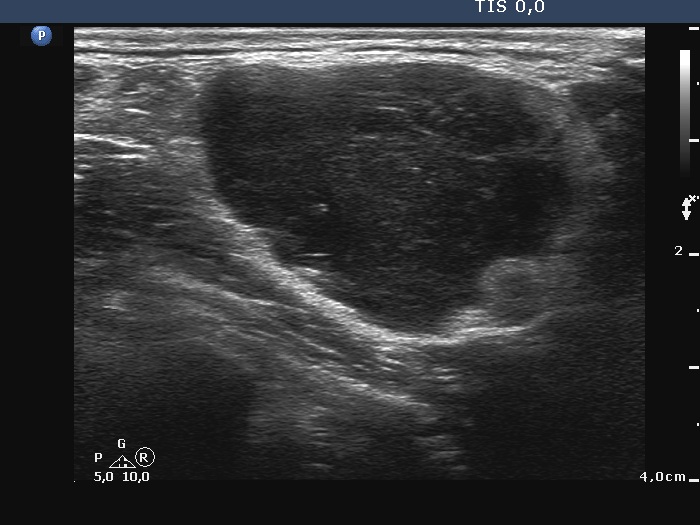

Palpation: A very firm node in the left supraclavicular region.

Ultrasonography. The thyroid was echonormal and intact. There was a large and several small lymph nodes in the left supraclavicularegion. The nodes did not have hilum, the largest one presented with irregular margins and irregular vascularity. The diameters of the node were 31x23x45 mm, width, depth, length, respectively.